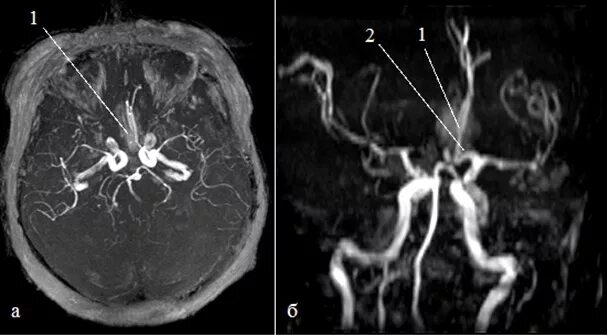

Аневризма головного мозга на кт